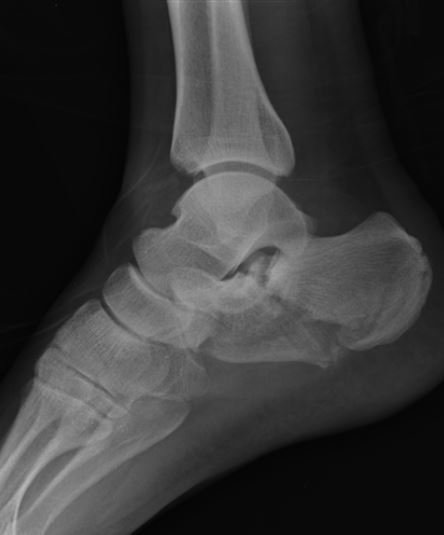

A 29-year-old male sustains the isolated lower extremity injury shown in Figure A. During open reduction, what structure must be kept intact in order to protect the remaining blood supply to the talar body?

This is a Hawkins 3 talar neck #

critical to preserve the deltoid ligament because the deltoid branch of the PT, which supplies the medial half of the talar body, is the only remaining blood supply.